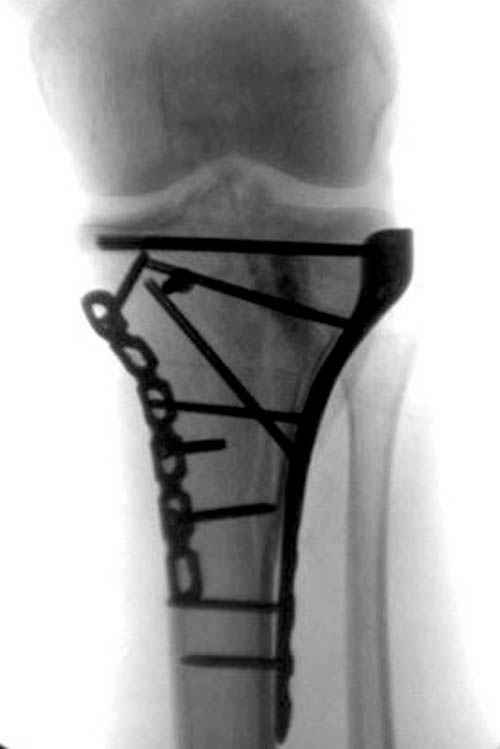

Уважаемые коллеги! В прошлую пятницу больной прооперирован - как и планировалось мыщелковая LCP от ChM. Малоинвазивно не получилось - один большой доступ :(. (но с минимальным скелетированием б/б кости). Наружный мыщелок собрали, но по контролю видно, что задне-медиальный отдел метаэпифиза смещен. Фиксировать не стали (?). 4-е сутки после операции - по м/тканям без проблем. Дополнительная иммобилизация синтетическим тутором.

Трудно поверить, что разрекламированная Ортопедическая школа Восточной Украины позволяет такие странные снимки? На прямом снимке сохранен общий контур плато, но не известна судьба импрессии суставной поверхности. На полубоковой?, оставлен без репозиции задне-медиальный отдел, и навряд ли после такой фиксации можно удовлетвориться результатом.

Такая ситуация характерна для многих, когда принимается ошибочное решение, т.е пытаются фиксировать одним имплантом переломы двух мыщелков. Латеральная пластина приемлема только для тех случаев, когда сохраняется интактным медиальный диафизарный кортекс и отсутствует фрагментация на верхушке медиального перелома.

При сложных переломах тибиал плато для своего рода Damage Control мы иногда применяем поэтапную тактику. Сперва оперируется одна сторона, а потом после рекондиции мягких тканей окончательный этап.

Если состояние мягких тканей позволяет, я бы предложил такой метод для вашего больного. Без предварительного планирования будет трудно, но шанс не надо упускать. Всего несколько дней после операции, и такая тактика лучше, чем недовольный молодой пациент.

Доступ к медиальной стороне задний или медиальный, через pes или в пространстве между medial gastroc мышцы.